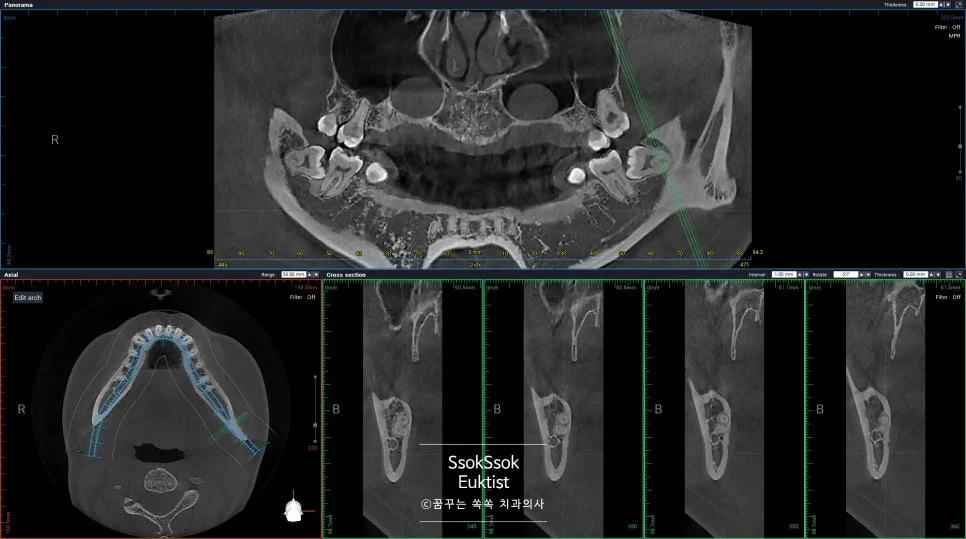

오른쪽 아래 사랑니의 경우 신경관과 바로 붙어 있습니다.

오른쪽 아래 사랑니 — 신경관과 바로 붙어 있는 상태

하지만 그보다 더 걱정인 건 사랑니 뿌리의 모양인데요.

사랑니 뿌리가 서로 다른 방향으로 휘어 있는 구조

뿌리가 서로 다른 방향으로 휘어 있어 한 번에 나올 수 없는 상황인데요. 이런 경우 뿌리가 전부 나오지 않고 뿌리의 조각이 일부 남아 있게 될 수 있습니다.